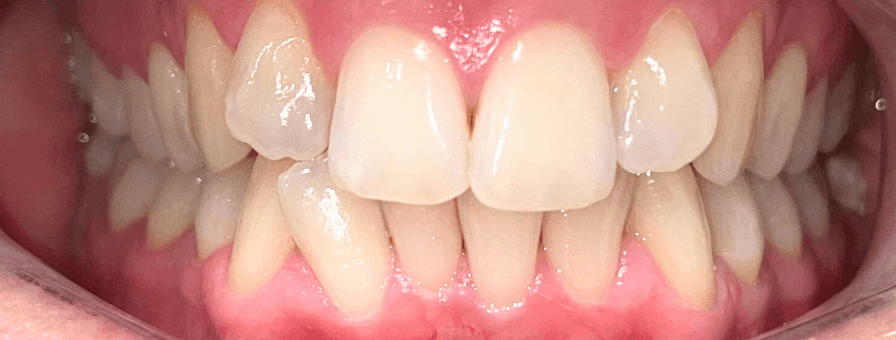

Tratament Ortodontic Fix pentru Înghesuiri Severe

Am tratat cazul cu aparat fix bimaxilar, după o evaluare completă a complexității și a necesarului de spațiu. Cazul a fost finalizat în aproximativ 1 an.